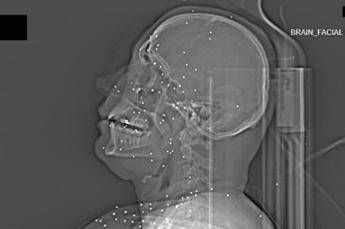

(Adnkronos) – Il Guardian, quotidiano britannico da anni impegnato nel documentare violazioni dei diritti umani, ha pubblicato un’inchiesta che aggiunge un tassello crudo e difficilmente contestabile alla comprensione della repressione delle proteste in Iran. Non si tratta di testimonianze verbali, non di racconti filtrati dalla distanza o dalla propaganda, ma di immagini mediche: radiografie e Tac. Fotografie in scala di grigi che mostrano, letteralmente, la violenza impressa nei corpi.

Il volto di Anahita – nome di fantasia, poco più che ventenne – appare come un cielo notturno attraversato da punti luminosi. Piccole sfere metalliche, da 2 a 5 millimetri, disseminate sul viso, nelle orbite oculari, persino nella massa scura del cervello. Sono proiettili “birdshot”, pallini da caccia sparati da un fucile a pompa. A distanza ravvicinata, spiegano gli esperti, non sono affatto “meno letali”: possono frantumare ossa, devastare tessuti molli, perforare facilmente un bulbo oculare. Anahita ha perso almeno un occhio, forse entrambi.

Quell’immagine non è un caso isolato. Fa parte di oltre 75 set di esami diagnostici provenienti da un singolo ospedale di una grande città iraniana, raccolti nel corso di una sola serata, durante la stretta repressiva di gennaio. Una concentrazione temporale che, già di per sé, racconta una dinamica da “mass casualty”, evento con numerose vittime simultanee, tipico degli scenari di guerra o dei grandi disastri.